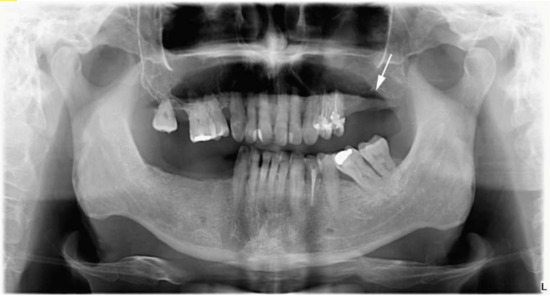

1.1. Case Report